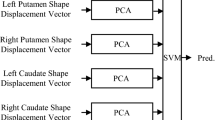

This work introduces a robust framework for predicting Deep Brain Stimulation (DBS) target structures which are not identifiable on standard clinical MRI. While recent high-field MR imaging allows clear visualization of DBS target structures, such high-fields are not clinically available, and therefore DBS targeting needs to be performed on the standard clinical low contrast data. We first learn via regression models the shape relationships between DBS targets and their potential predictors from high-field (7 Tesla) MR training sets. A bagging procedure is utilized in the regression model, reducing the variability of learned dependencies. Then, given manually or automatically detected predictors on the clinical patient data, the target structure is predicted using the learned high quality information. Moreover, we derive a robust way to properly weight different training subsets, yielding higher accuracy when using an ensemble of predictions. The subthalamic nucleus (STN), the most common DBS target for Parkinson’s disease, is used to exemplify within our framework. Experimental validation from Parkinson’s patients shows that the proposed approach enables reliable prediction of the STN from the clinical 1.5T MR data.